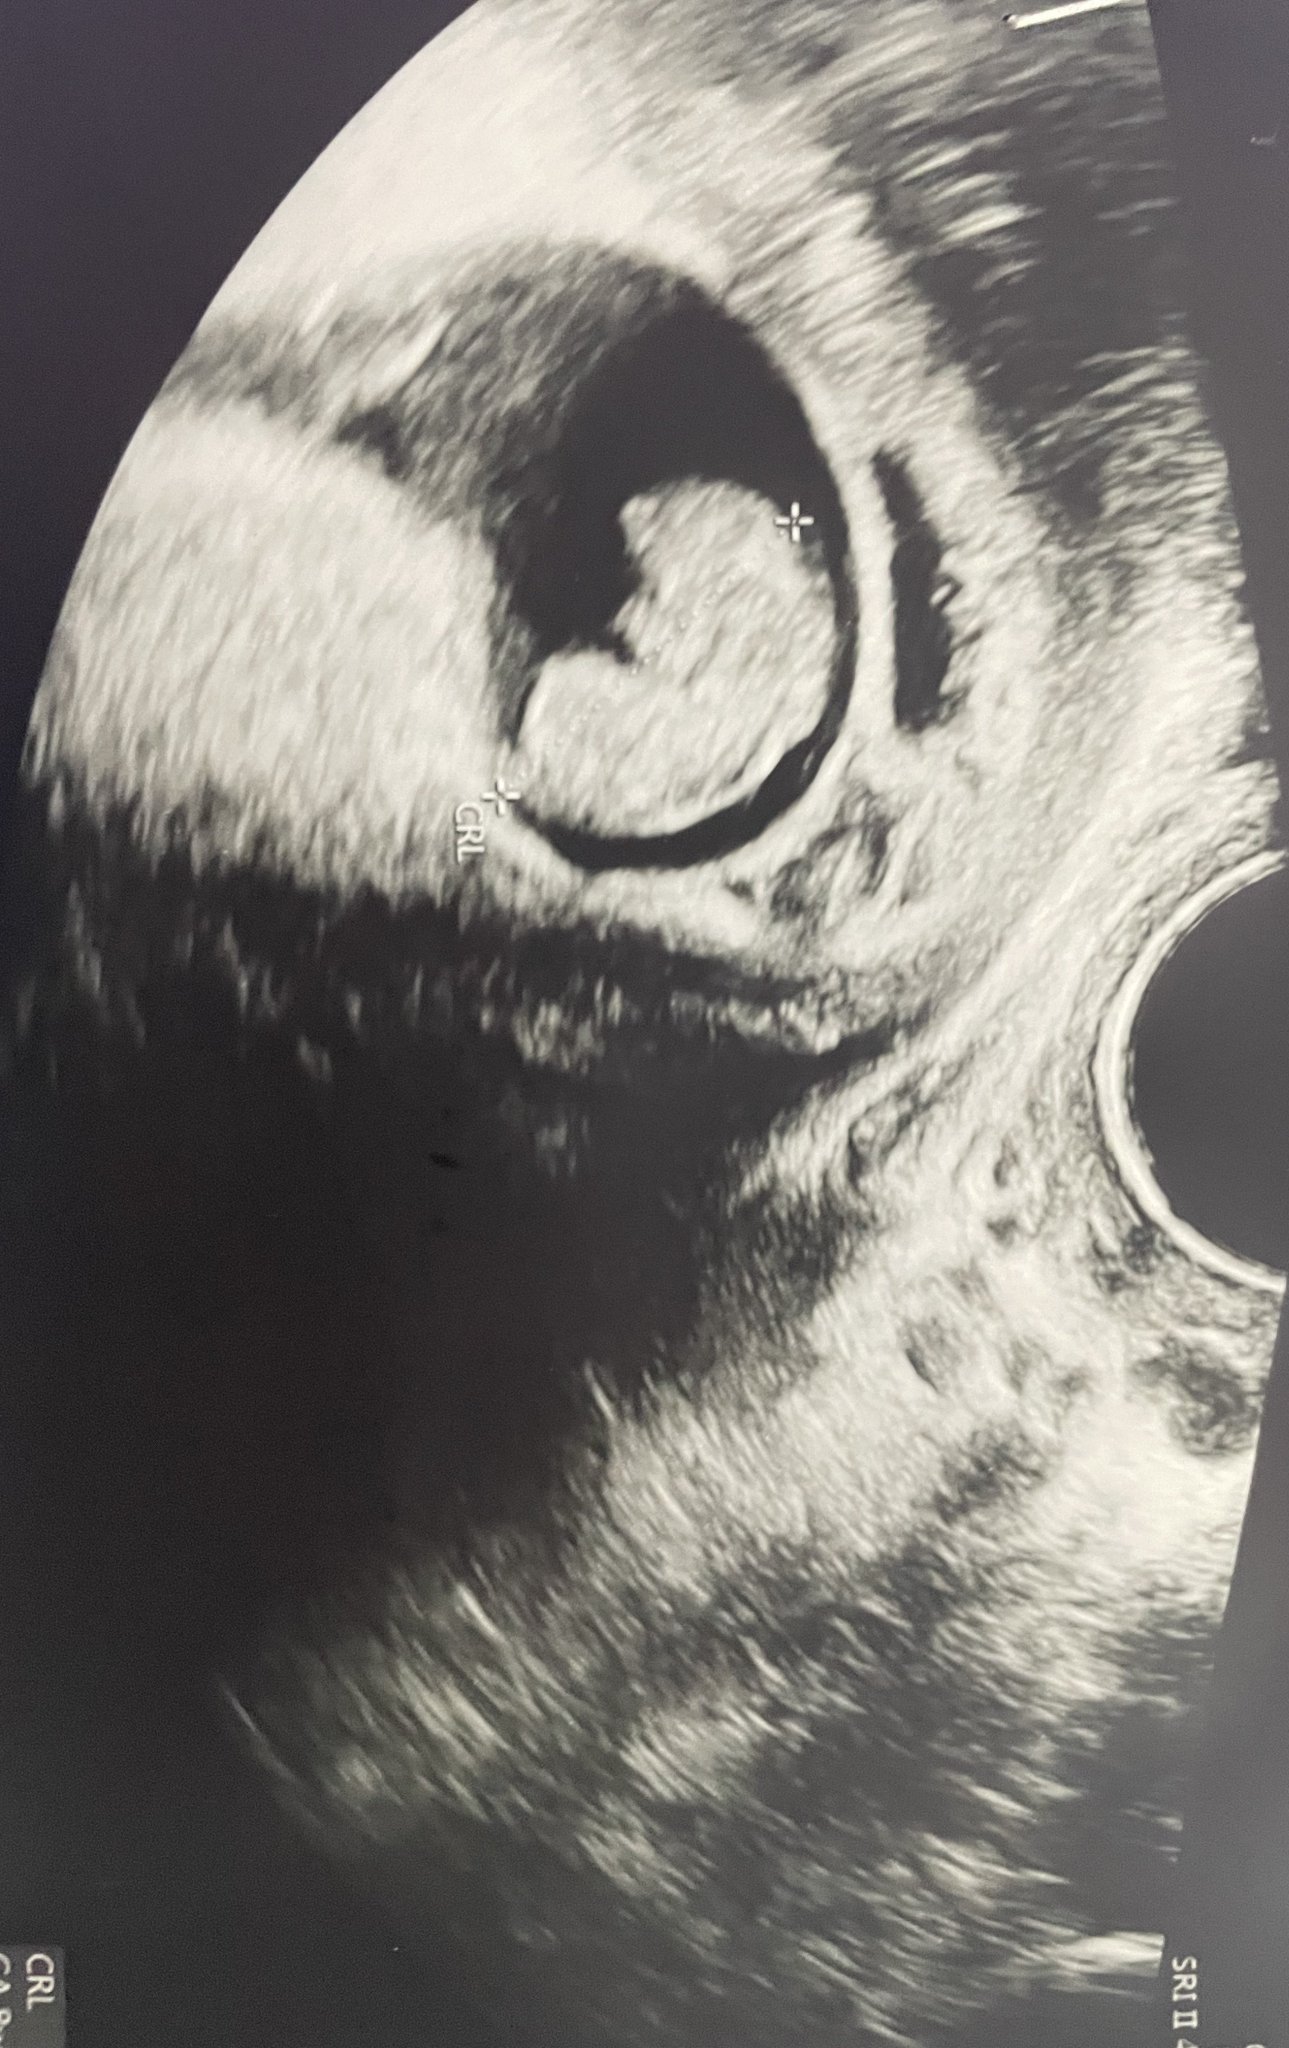

прикачвам тази снимка тук доктора каза че е кухо яйце според вас кухо яйце ли е ?

(((